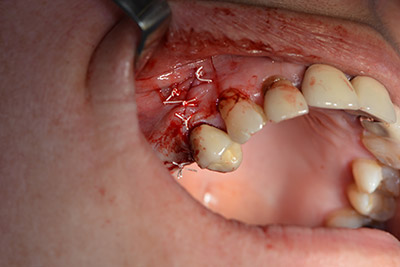

Eine resorbierbare Membran bildet die Barriere nach bukkal und deckt das Augmentat ab. Zum Schluss wird speicheldicht vernäht. (Abb. 15 bis 19).

speicheldichter Wundverschluss.

Abb. 19